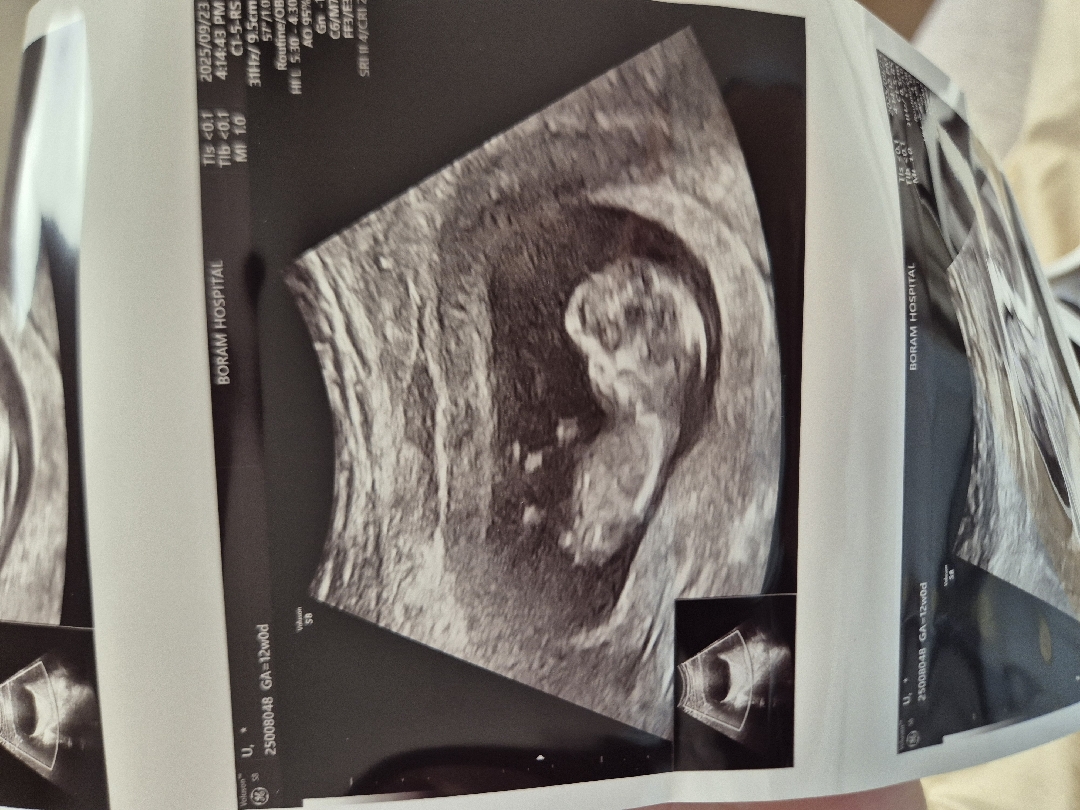

12주 0일 아가 각도법 참견해주세요😍

안녕하세요! 12주 0일차에 1차 기형아검사랑 초기 입체초음파 보고왔습니다! 진료내내 아가가 너무 움직여서 잘안보여주긴 했지만! 그래도 여러분들의 지혜를 구해봅니다🩷 예쁜 딸일까요? 아들일까요?